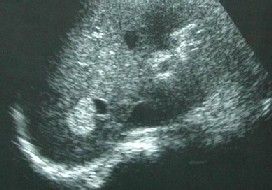

Η διάγνωση γίνεται συνήθως με Υπερηχογράφημα ήπατος αλλά αν χρειαστεί μπορεί να υποβληθεί κάποιος και σε έλεγχο με Μαγνητική (MRI) ή Αξονική (CT) τομογραφία άνω κοιλιάς.